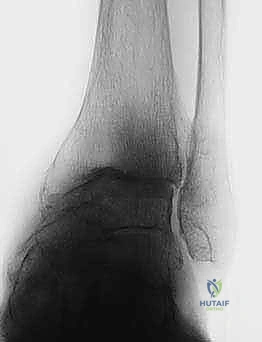

FIG 6 • The TNK ankle replacement for rheumatoid arthritis of the ankle (cemented replacement). A. Preoperative AP view. B. Preoperative lateral view. C. Postoperative AP view 2 years 6 months after the surgery. D. Postoperative lateral view.